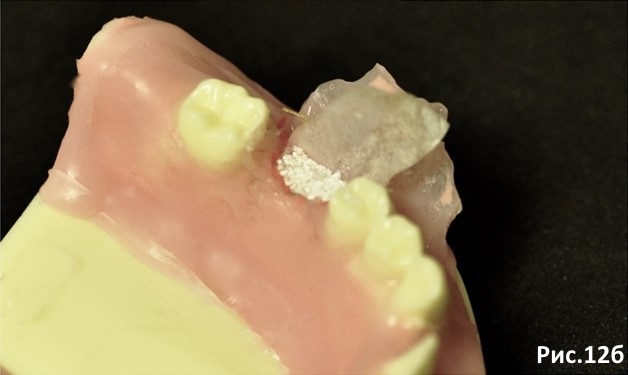

Перекрываем Остеоматрикс материалом Биоимплант ГАП защищая коллагенсодержащий материал от прорастания в него мягких тканей. Рис.12а Рис. 12б